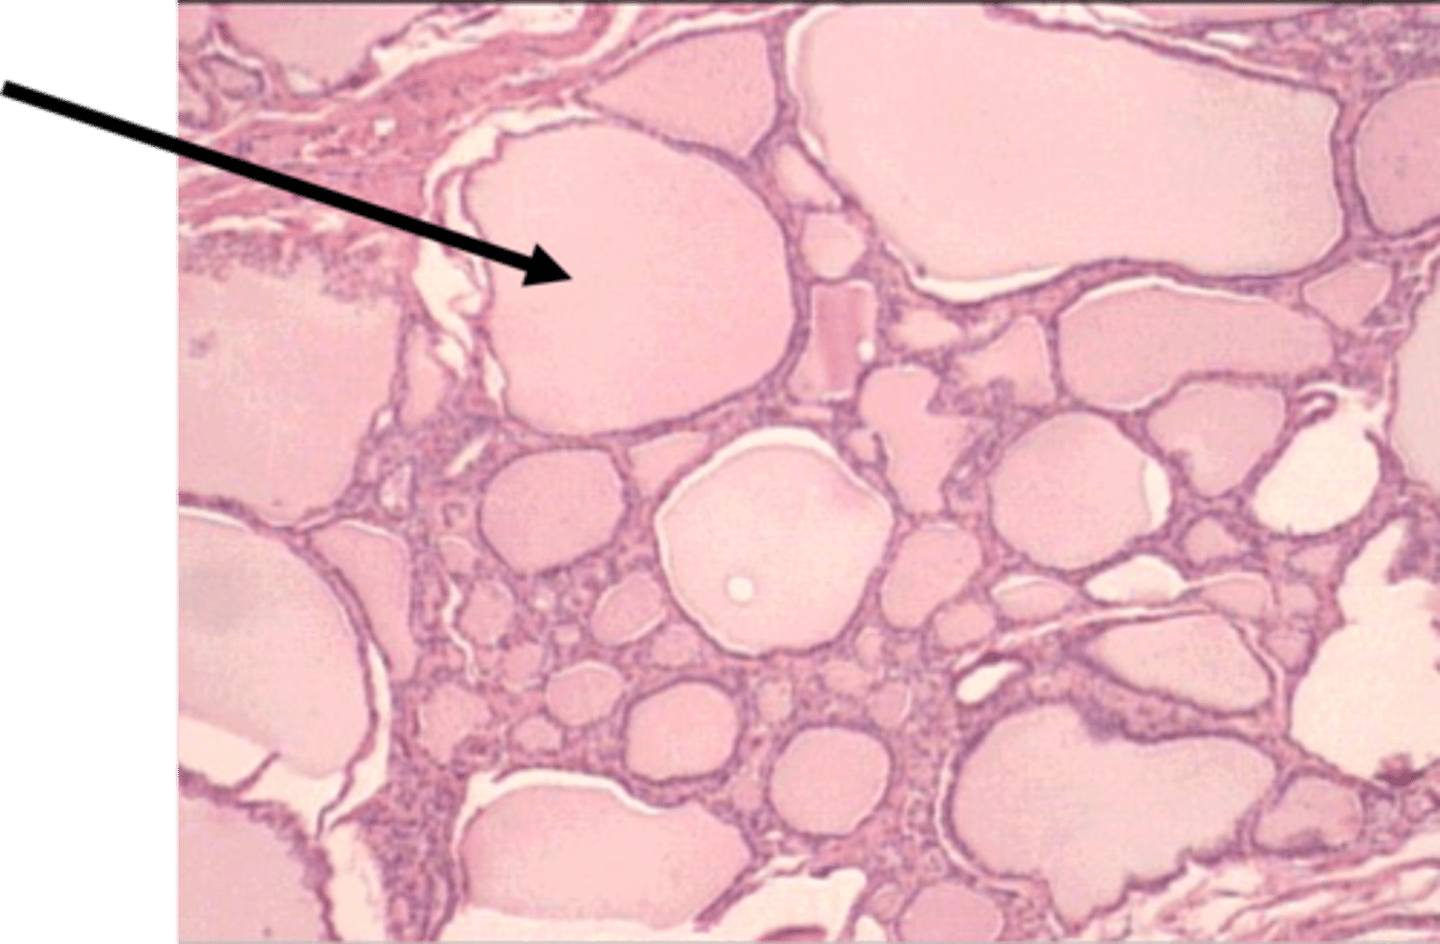

Thyroid gland

Colloid-filled follicle

Follicular cell